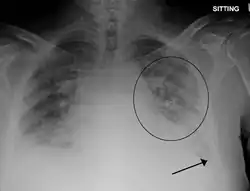

Pulmonary edema with small pleural effusions on both sides | |

Chest X-ray has been used for many years to diagnose pulmonary edema due to its wide availability and relatively cheap cost.[4] A chest X-ray will show fluid in the alveolar walls, Kerley B lines, increased vascular shadowing in a classical batwing peri-hilum pattern, upper lobe diversion (biased blood flow to the superior parts instead of inferior parts of the lung), and possibly pleural effusions. In contrast, patchy alveolar infiltrates are more typically associated with noncardiogenic edema.[3]